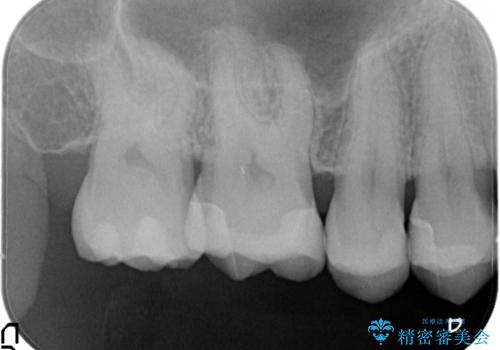

- 金属のインレーを除去を希望されて来院されました。

セラミックインレーにて治療を行なっております。

e-max プレスインレーにて修復治療を行っているため適合性及び審美性の高い治療を行うことができます